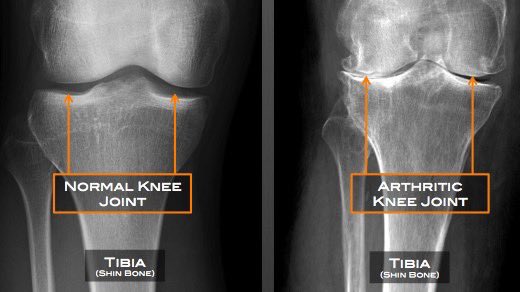

آلام المفاصل💡

أحسست بآلام المفاصل، طبيبك أخبرك انها بداية خشونة وصف لك المسكنات و العلاج الطبيعي وبس!!

في آلام المفاصل خصوصا بداية الخشونة التي يعاني منها اغلب المرضى! الطبيب يشخص لك الحالة